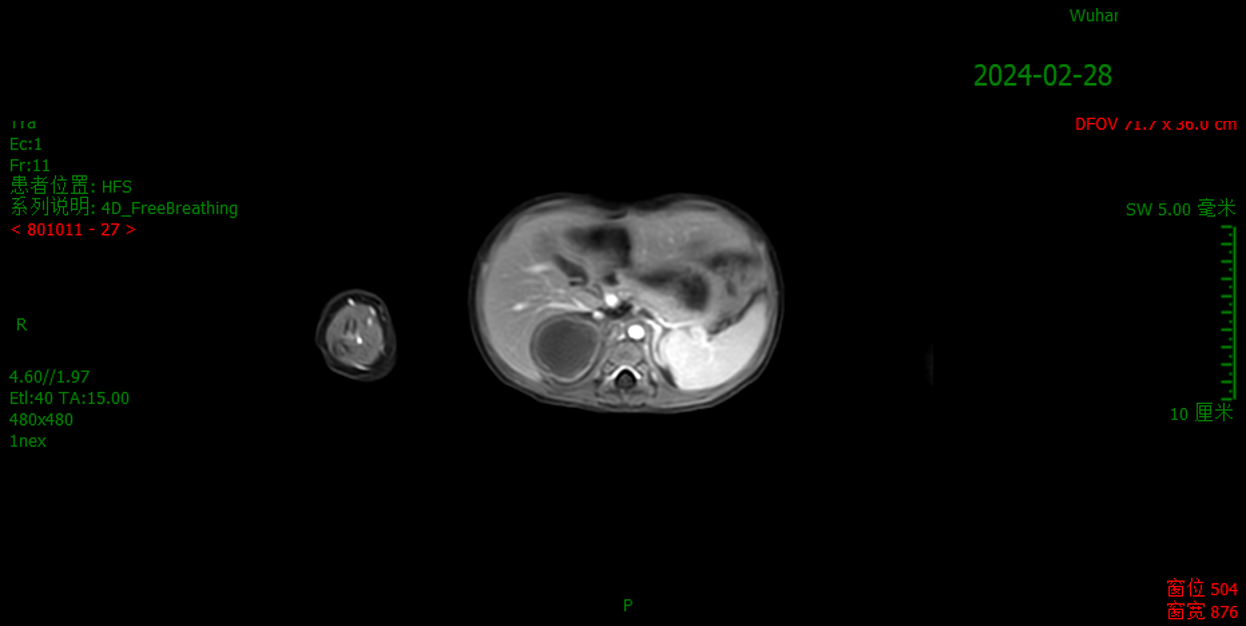

2024.02.28 诱导化疗后疗效评价:

MRI:“腹膜后肿瘤切除术”后,术区脂肪间隙稍显混浊;肝右叶-右肾上方多发等信号结节/团块状影,大者约35×31mm,强化不明显(仅包膜稍强化)。